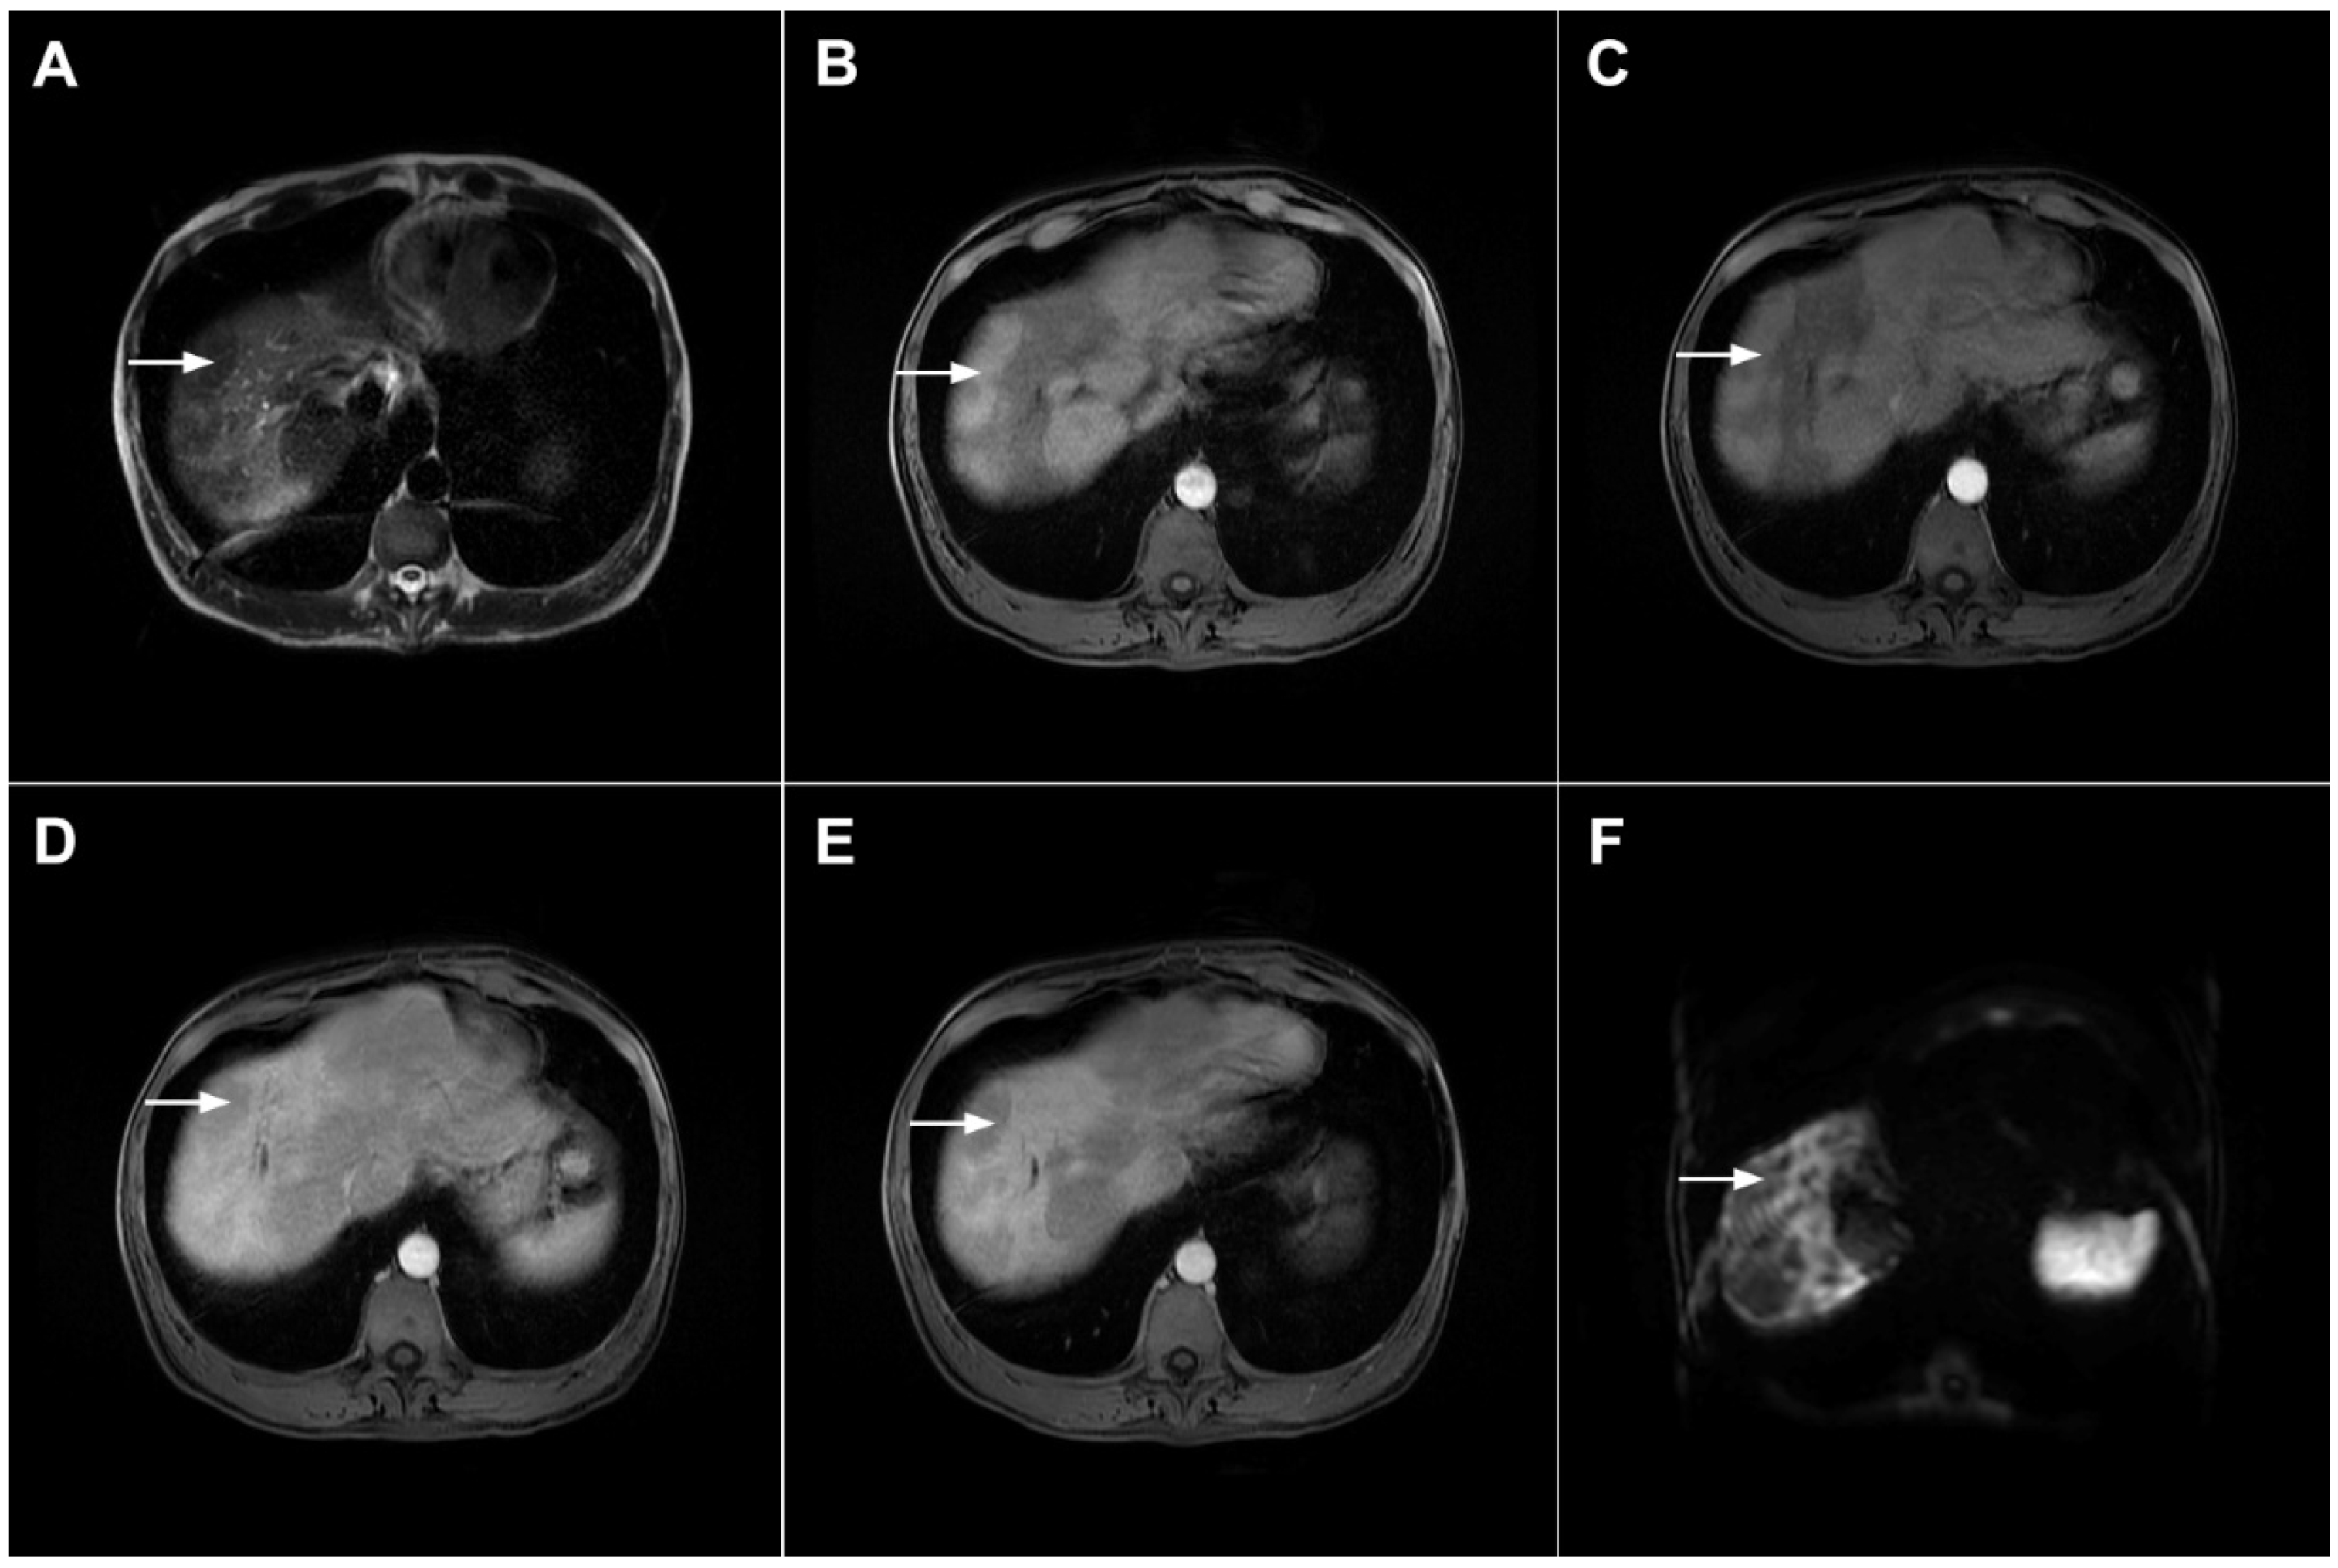

MRI features of focal confluent fibrosis may mimic mICC [30]. Since both mICC and confluent fibrosis develop in the same group of patients, it is very important to draw a distinction between these two entities. Similarly to mICC, focal confluent fibrosis shows mild to moderate hyperintensity on T2-weighted images and capsular retraction [30]. However, while mICC presents as a lobulated lesion associated with capsular retraction, focal confluent fibrosis is typically seen as a wedge-shaped lesion radiating from the porta hepatis with straight or concave borders and the base in the subcapsular region [15,30]. Focal confluent fibrosis commonly involves segments IV, VII, or VIII corresponding to the drainage territory of the middle hepatic vein [32,33]. Dilatation of proximal intrahepatic biliary ducts is frequently seen in mICC, whereas it is not observed in focal confluent fibrosis [15]. Focal confluent fibrosis lacks arterial vascularity, with homogeneous mild enhancement during the portal venous phase and strong enhancement in the delayed phase (Figure 8) [34]. Progressive enhancement seen in focal confluent fibrosis, attributed to the accumulation of contrast agents in the extracellular compartment, should not be confused with postcontrast behavior of mICC, which is irregular and heterogeneous [15,30]. Occasionally mild arterial phase enhancement may be present in focal confluent fibrosis, which can be explained by immature fibrosis and inflammation occurring in the early phase of development [30]. In such cases, other imaging features such as the shape of the lesion, associated biliary dilatation, satellite nodules, and lymphadenopathy must be considered. Concerning relationship with vascular structures, it should be noted that trapped and crowded vessels may be seen within confluent fibrosis mimicking vascular encasement, which is frequently present in mICC [30]. The use of hepatobiliary contrast agents usually does not provide additional information to distinguish between mICC and focal confluent fibrosis since both lesions are hypointense in the hepatobiliary phase [35]. Nevertheless, the visualization of recently described cloud signs favors the diagnosis of mICC [19]. In addition, the target sign on high b-value DWI is frequently observed in mICC, whereas focal confluent fibrosis displays only slight homogeneous diffusion restriction, but with ADC the values slightly higher than those of mICC [16].

Figure 8.

Focal confluent fibrosis in a 42-year-old man with long-standing primary sclerosing cholangitis. The T2-weighted image (A) shows a band like a slightly hyperintense lesion (arrow) at the dome of the liver. On the plain T1-weighted image (B) the lesion (arrow) is hypointense without arterial vascularity (C) while homogeneous progressive enhancement is seen in the portal venous (D) and delayed phases (E). The lesion (arrow) shows high signal intensity in DWI (F).